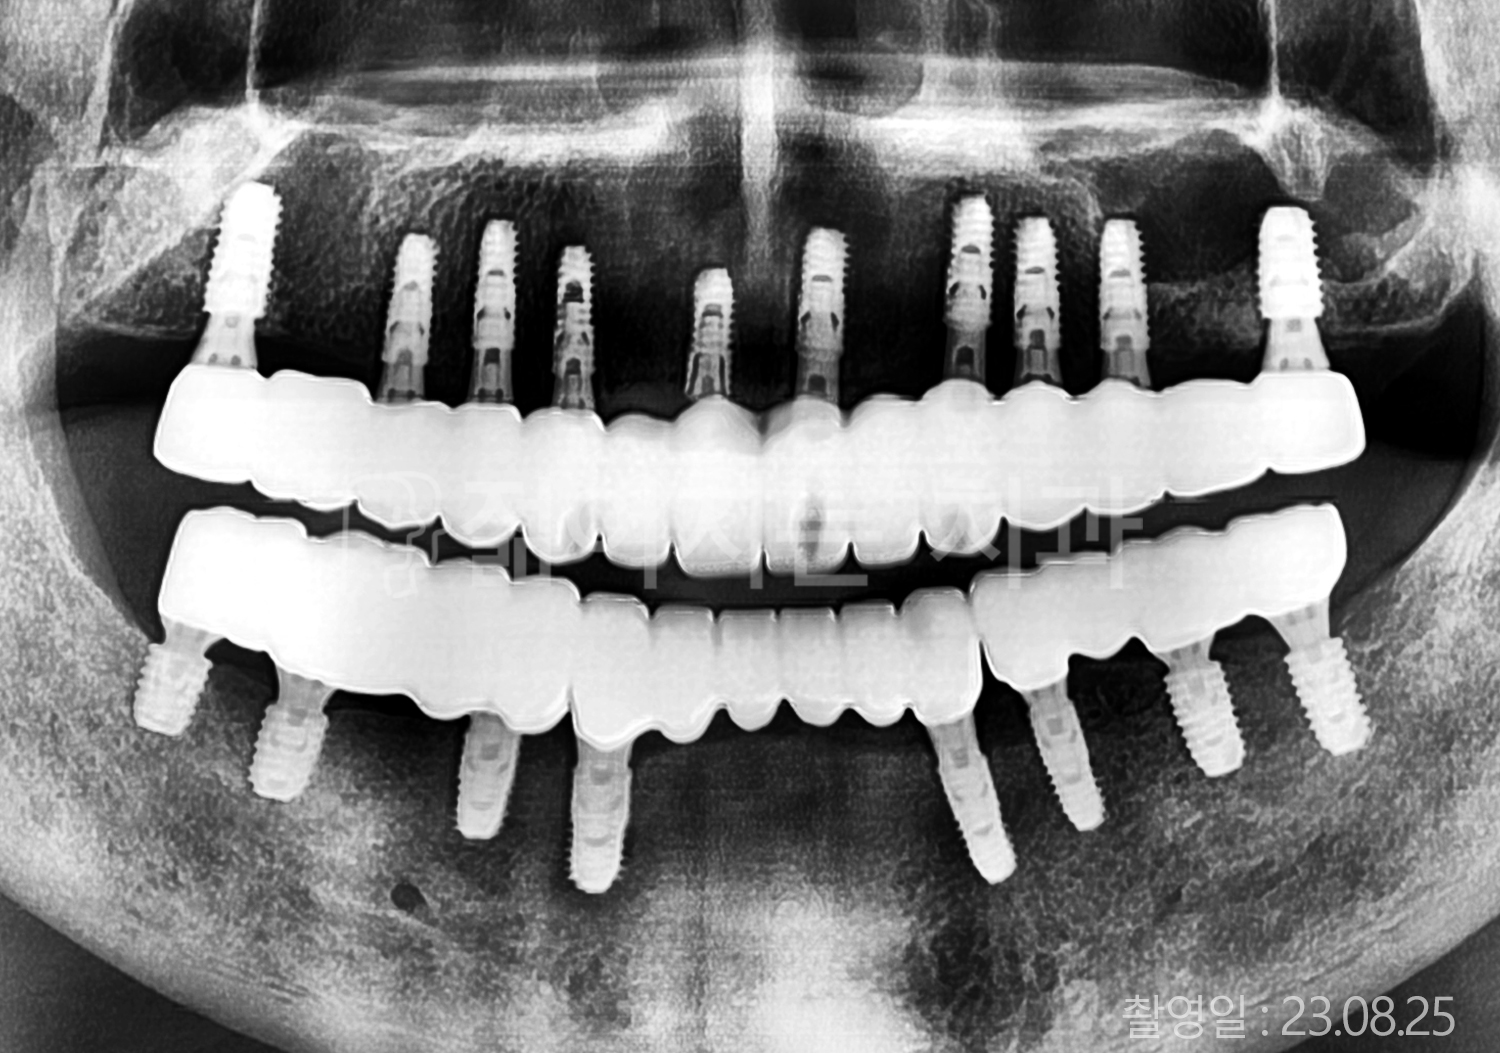

• 60대 고혈압, 고지혈증 전체치아 10개 이상 임플란트

• 70대 전체치아 10개 이상 임플란트

• 60대 전체치아 10개 이상 임플란트

• 50대 전체치아 10개 이상 임플란트

• 50대 고혈압, 고지혈증 전체치아 10개 이상 임플란트

• 60대 고혈압, 당뇨, 고지혈증 전체치아 10개 이상 임플란트

• 80대 고혈압, 당뇨, 골다공증 전체치아 10개 이상 임플란트

• 60대 고혈압 전체치아 10개 이상 임플란트

• 60대 고지혈증 전체치아 10개 이상 임플란트

• 60대 당뇨 전체치아 10개 이상 임플란트